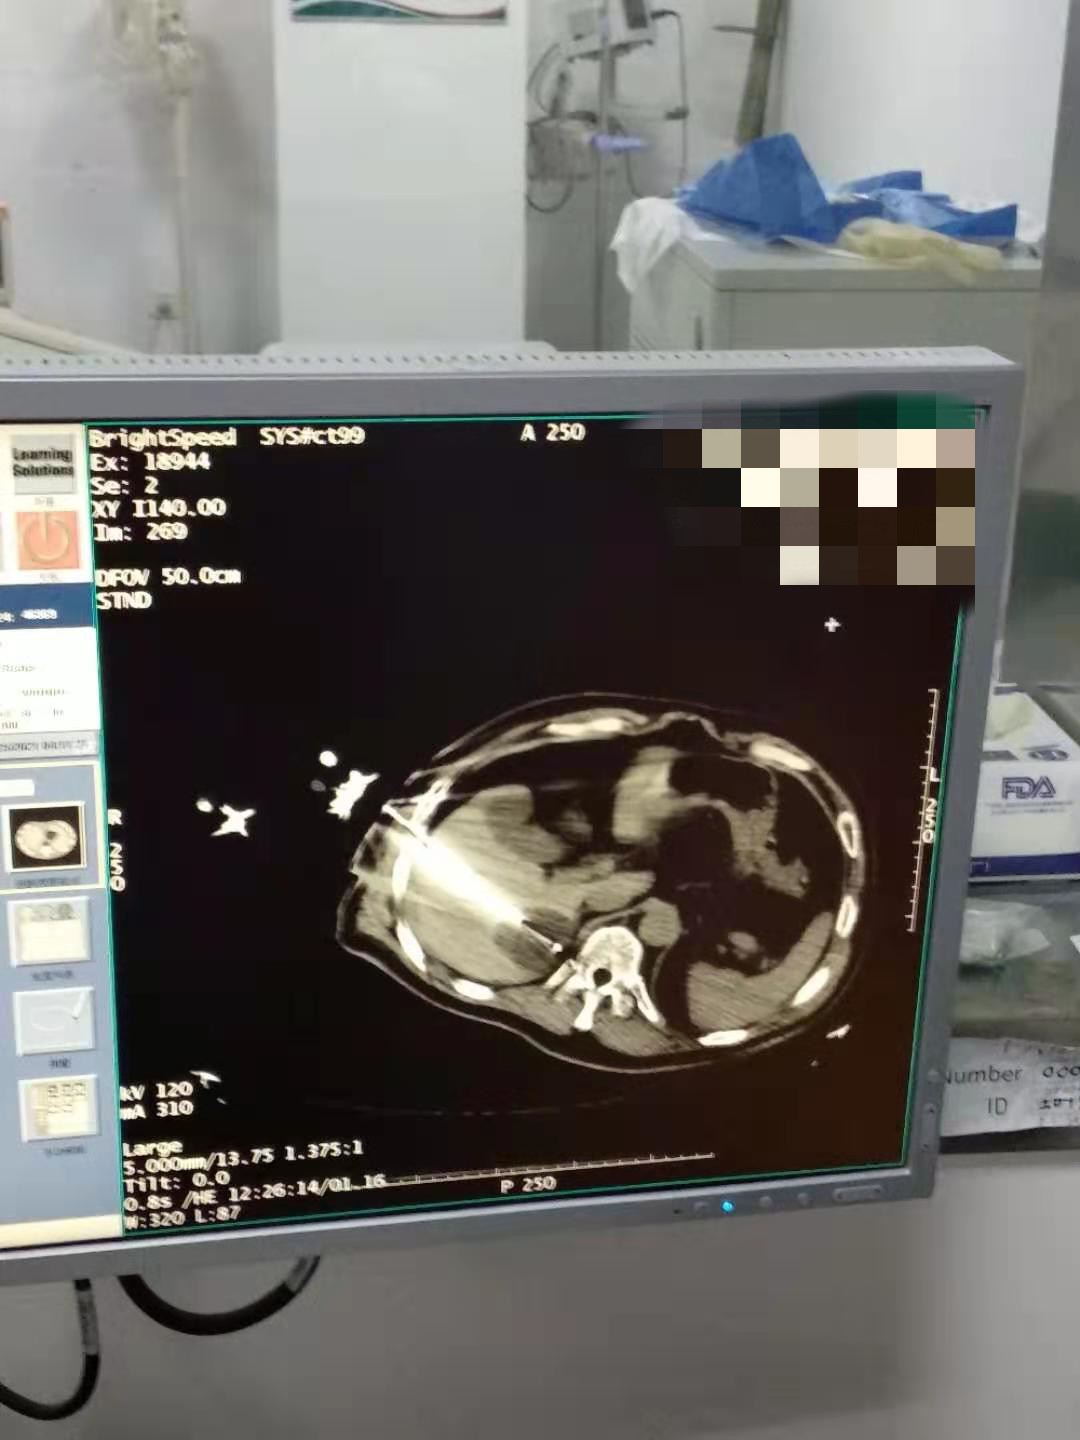

2021年2月份肝部氩氦刀手术